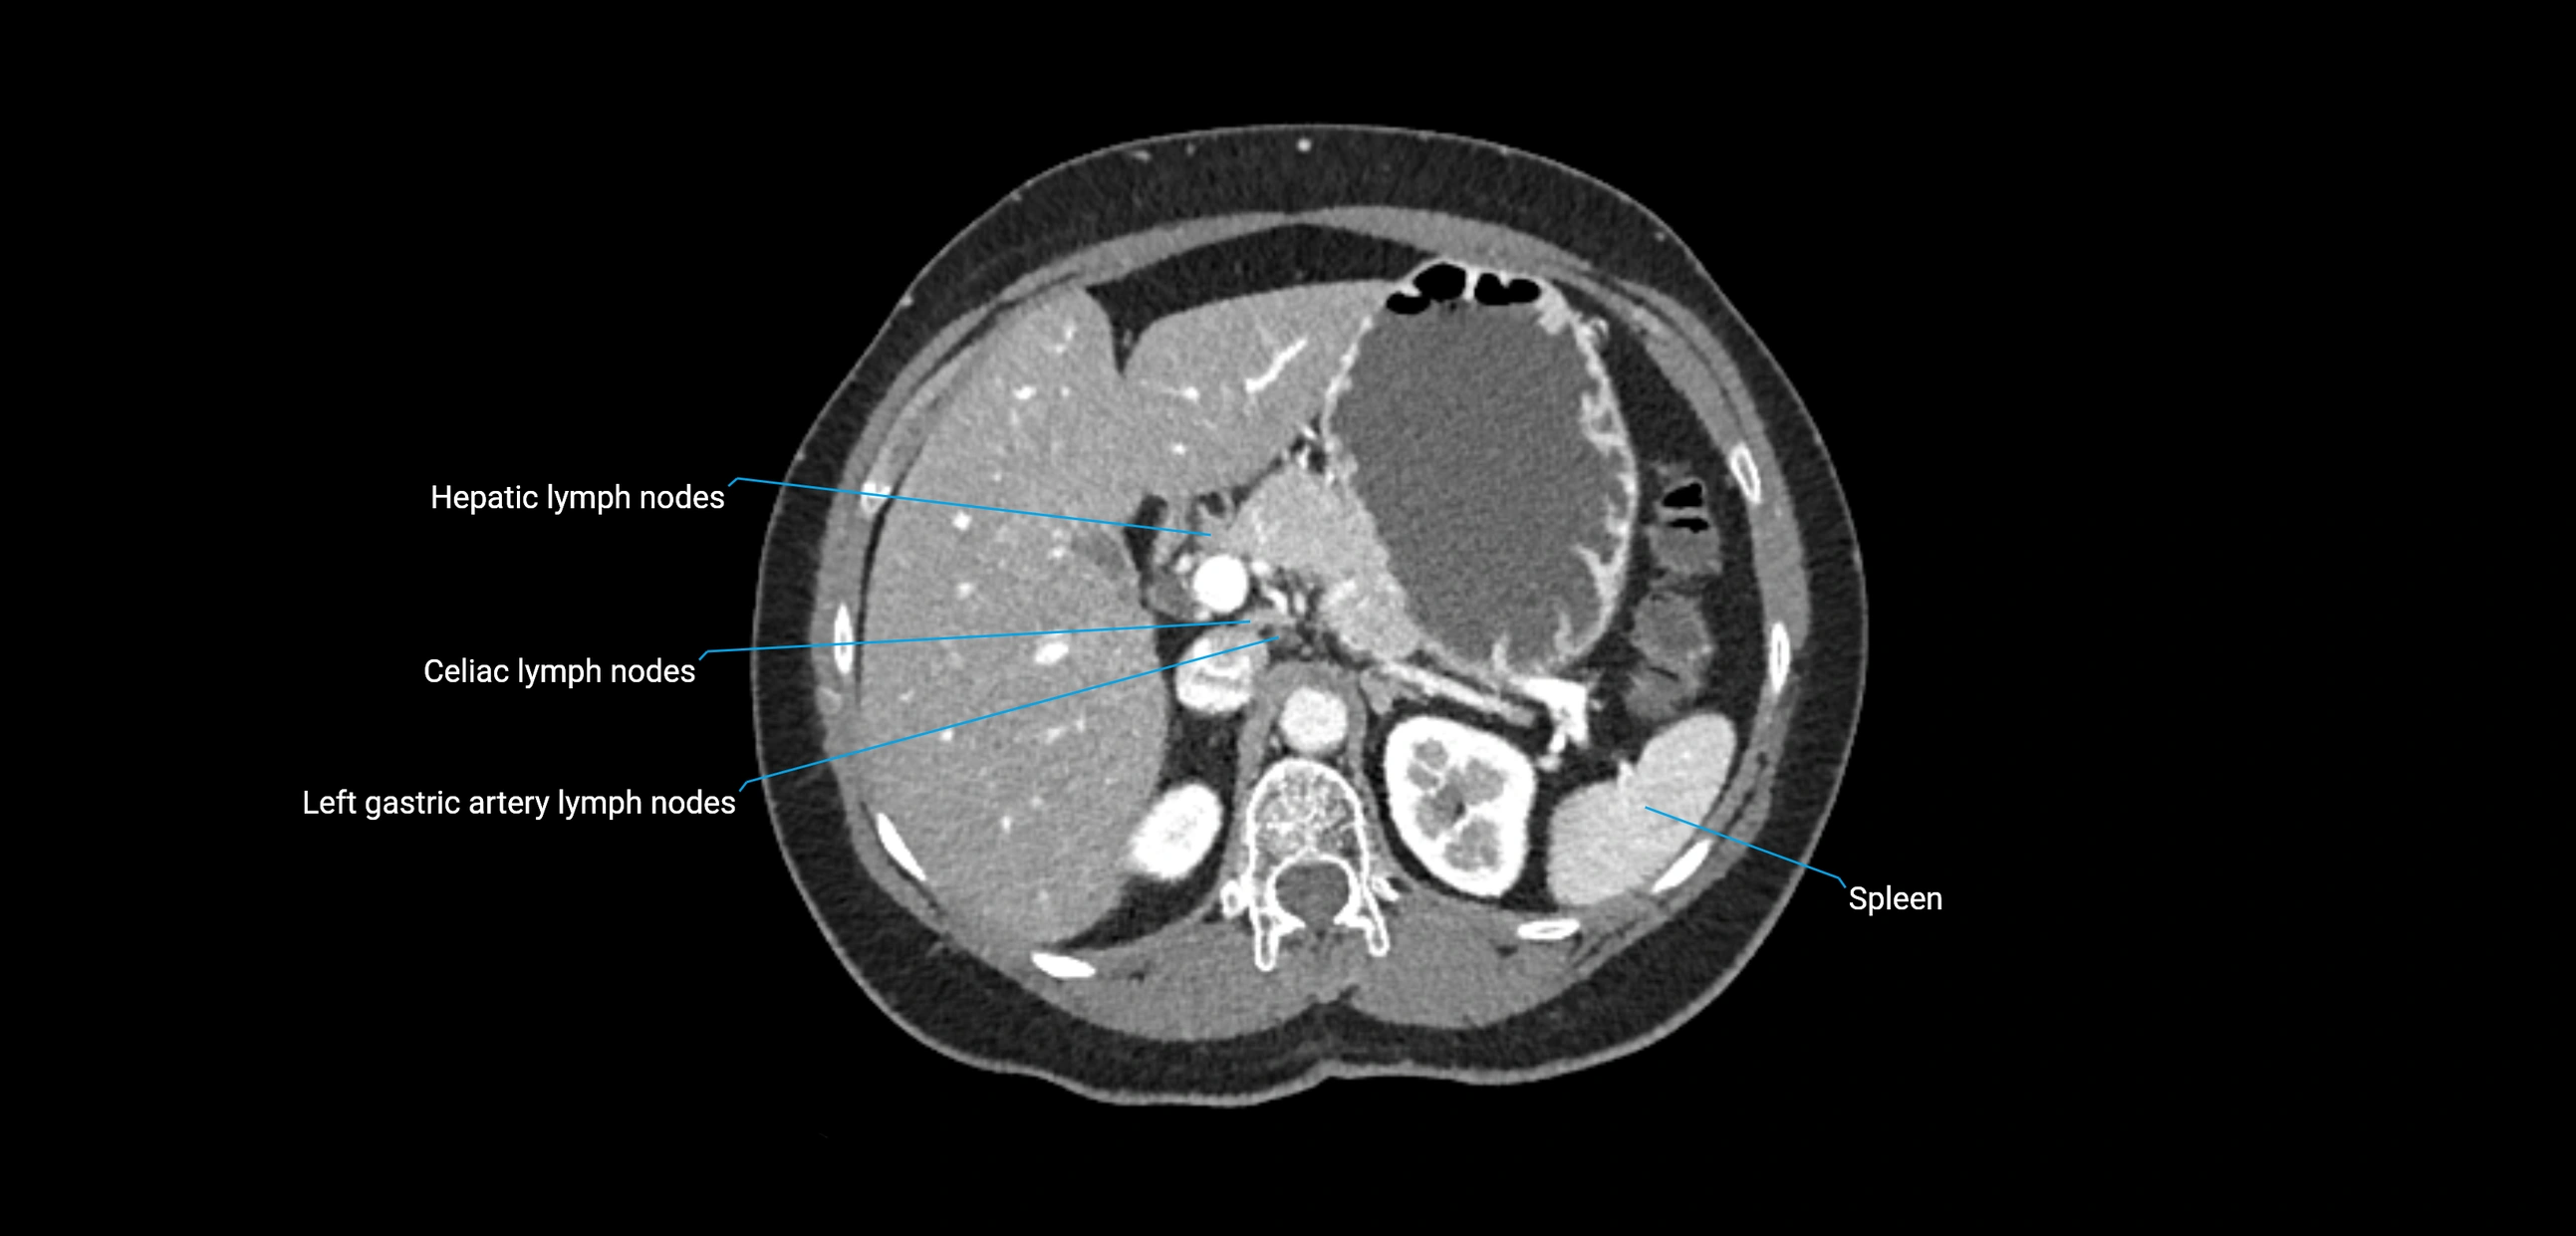

CT Appearance

CT Post-Contrast:

• Normal nodes enhance homogeneously

• Malignant nodes may show heterogeneous enhancement, central necrosis, or conglomerate formation

• Size >1 cm short axis is suspicious, though morphology and distribution are equally important

CT image

image